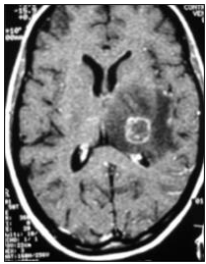

Uma paciente com 23 anos de idade foi admitida na emergência com quadro de crise convulsiva tônico-clônica generalizada. Sua mãe relatou que, nos últimos 15 dias, a paciente apresentou febre vespertina e cefaleia holocraniana. Procurou atendimento médico em duas ocasiões, nas quais foram prescritos apenas sintomáticos.

Ao exame, a paciente se encontrava emagrecida, hipocorada, desidratada, acianótica, anictérica, afebril, com dispneia e esforço respiratório. Candidíase oral e leões múltiplas por molusco contagioso em região genital. Diarreia. PA 90 x 55 mmHg, FC 110 bpm, FR 22 irpm, sat. O2 70. Gasometria revelou acidose metabólica. A paciente foi submetida à sedação, TOT e acoplada à VM. Toda medicação de suporte foi instituída, em especial a fenitoína venosa. Hemograma revelou anemia e linfopenia.

A imagem da tomografia de crânio com contraste revelou lesão anelar captante de contraste com edema perilesional e efeito de massa apagando parcialmente o ventrículo esquerdo e leve desvio da linha média.

O teste rápido para detecção do HIV foi reator. A mãe relatou que a paciente é alérgica à sulfa.

Baseado no relato, na imagem da tomografia computadorizada do crânio, e considerando a infecção oportunista neurológica grave mais comum na aids, assinale a opção que apresenta o diagnóstico e o tratamento específico mais indicado para o caso.